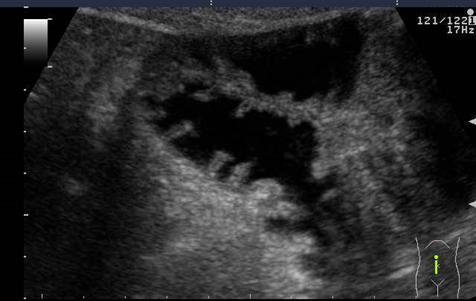

Uzunmüddətli anamnez, arıqlama, qarında kütlənin əllənməsi, tutmaşəkilli qarın ağrıları, duodenal keçməzliyə bağlı qusma (requrqitasiya) və ektopik mədə mukozasının xoralaşmasına görə qanaxma (qanlı qusma, melena) hadisələri, diaqnostik şübhə əlamətləridir. Əksər xəstələrdə Rh-ji müayinə hesabına diaqnoz qoyulmur. Şübhəli hadisələrdə kontrastlı KT, MRT və laparoskopiya müayinələrinin rolu böyükdür. Şüa müayinələri zamanı OBB-ın mənfəzinin dolma defektinə görə daralması müəyyən edilir (şək 3. ).

Şək. 3 Onikibarmaq bağırsağın ikiləşməsi (mənfəzin dolma defekti hesabına daralması)